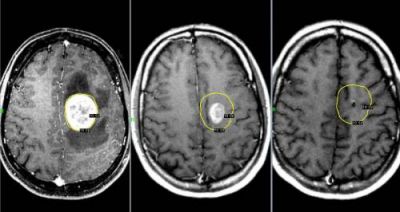

Опухоли мозга

Злокачественные опухоли характеризуются быстрым прорастанием в другие ткани с их последующей трансформацией. При этом метастазы могут наблюдаться сразу в нескольких участках мозга.

Такие опухоли плохо лечатся, а на поздних стадиях их развития спасти человека практически невозможно.

Характер болевых ощущений — постоянный, по мере развития заболевания продолжительность приступов увеличивается. Когда человек двигается, болевые ощущения усиливаются. Сначала они локализуются в области опухоли, потом, по мере увеличения внутричерепного давления, переходят в лобную и затылочную часть. Наиболее сильный дискомфорт наблюдается в ночное и утреннее время из-за скопления жидкости. Вены не справляются с оттоком крови, поэтому к болям прибавляются отёчность и застои. Боли давящие, распирающие, пульсирующие.

К головным болям затем добавляется рвота. При физической нагрузке или кашле болевые ощущения усиливаются, появляется двоение в глазах, временами исчезает зрение. Голова кружится, у пациента нарушается координация движений. Могут неметь конечности, ослабляется тонус мышц.

Иногда бывают эпилептические припадки, путается сознание.

Диагностирование

Для диагностики используется МРТ мозга, ПЭТ, КТ мозга, ангиография и другие методы.

Опухоль мозга

Данное новообразование появляется в тканях мозга и может быть как злокачественным, так и доброкачественным. Последнее можно вылечить без хирургического вмешательства. Злокачественная опухоль растет очень быстро и дает метастазы. Поэтому лечению заболевание поддается с трудом, особенно на поздних стадиях.

При данном заболевании боль ощущается постоянно, а во время движения только усиливается. Самые сильные боли бывают в утреннее и ночное время вследствие накопления избыточной жидкости в тканях. Характер боли — давящий, пульсирующий.

Помимо самой головной боли, постепенно появляются другие симптомы: